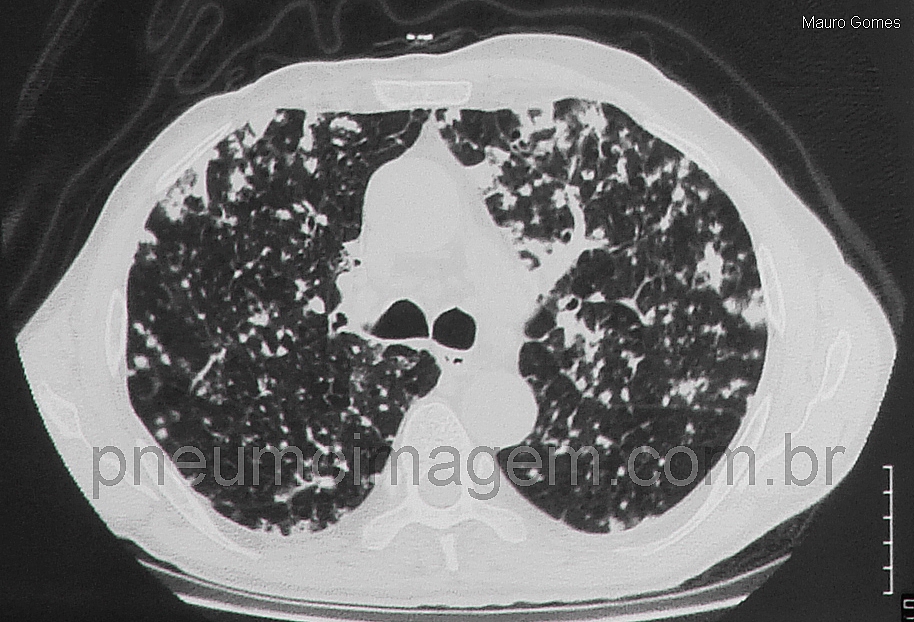

Entre os achados da TC que são sugestivos de propagação aerógena podemos encontrar nódulos centrolobulares especificamente persistentes e opacidades em ramificação (árvore em brotamento). Os nódulos tendem a ser agrupados e invariavelmente crescem nos controles seriados de imagens. Em alguns casos evoluem para doença confluente do espaço aéreo. Quando essas características são encontradas remotamente durante a evolução a partir de uma lesão pulmonar primária que provou ser um adenocarcinoma, e/ou em pacientes com história prévia de adenocarcinoma de pulmão tratado, a propagação aerógena intrapulmonar deve ser suspeitada. É importante ressaltar que as metástases aerógenas devem ser diferenciadas de múltiplas lesões síncrônicas no espectro do adenocarcinoma de pulmão.